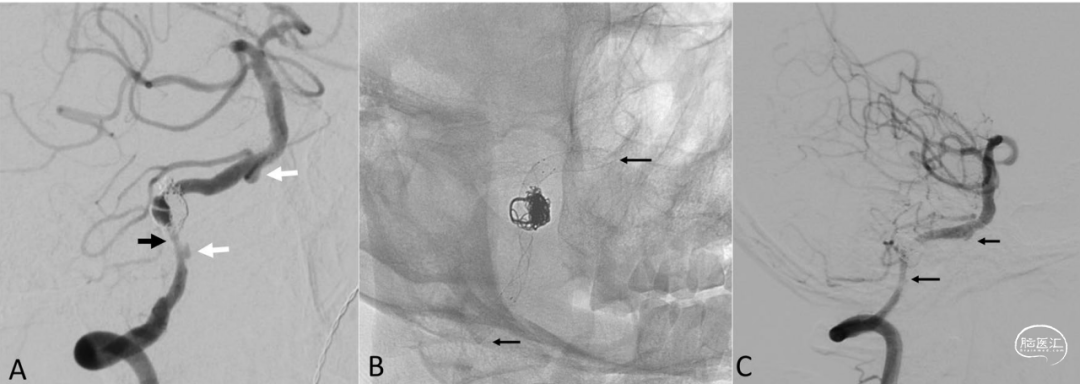

图2:一名63岁男性患者在支架辅助弹簧圈栓塞术后出现动脉瘤残留。

A. 数字减影血管造影,右侧颈内动脉注射,侧位视图,显示手术结束时动脉瘤残留部分仍有少量显影(箭头所示)。

B. 数字减影血管造影,右侧颈内动脉注射,前后位视图,未减影图像显示Neuroform Atlas支架(史赛克公司)远端位置较远。

C. 未减影图像,侧位视图,显示Pipeline栓塞装置在先前支架内完全展开。

D. 最终的未减影血管造影图像显示无血栓栓塞并发症的证据。

图3:一名66岁男性患者因椎动脉瘤破裂接受了LVIS支架辅助弹簧圈栓塞术,术后6个月复查。

A. 数字减影血管造影,斜位视图,显示动脉瘤残留(白色箭头)以及LVIS支架近端动脉狭窄(黑色箭头)。为改善载瘤动脉近端狭窄,进行了球囊血管成形术,并植入一枚Pipeline栓塞装置以覆盖3个动脉瘤。

B. 未减影图像显示先前植入的LVIS支架、弹簧圈以及Pipeline栓塞装置在支架内完全展开(箭头所示)。

C. 6个月随访时的减影血管造影图像显示动脉瘤完全闭塞,动脉狭窄得到改善